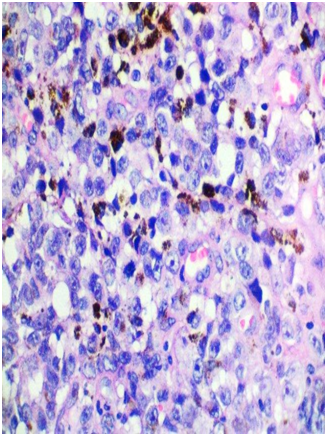

A 53-year-old female presented with one-month history of gross hematuria and increased frequency of urination. There was no past history of calculus. She did not have any medical comorbidities. She underwent hysterectomy after last childbirth at the age of 40 years. General physical examination and routine blood investigations were normal. CECT scan of whole abdomen showed 4.4x3.7x2 cm polypoid enhancing mass in urinary bladder with bladder wall thickening. Cystoscopy revealed blackish solitary papillary growth near bladder neck from 10 o’clock to 2 o’ clock position. A transurethral resection of the lesion was performed including deep muscular layers of the bladder wall. The respected specimen examination showed pigmented melanocytes infiltrating sub epithelial tissue below the transitional epithelium (Figure 1). Margins of resection were free, however, base was involved. Atypical melanocytes were seen at the margins of the tumor. Immunohistochemical study showed that tumor cells were positive for S-100 (Figure 2) and HMB-45 (Figure 3). They were negative for cytokeratin and SMA. Dermatologic, ophthalmologic, otorhinolaryngologic and proctologic evaluations were negative. Upper gastrointestinal endoscopy and colonoscopy were negative. Abdomen, chest and brain CT scans were negative. Bone scan was negative. These findings were consistent with primary malignant melanoma of urinary bladder. After thorough review of published scientific literature, we suggested radical cystectomy as the therapeutic option. The patient declined any further treatment so was given only symptomatic & supportive treatment. Nine months later, she presented with hematuria and back pain. PET-CT showed increased uptake in lumbosacral vertebrae and liver, suggestive of metastases. She was advised palliative radiotherapy to the painful bone metastases and continued to receive palliative care. She succumbed to complications caused by widespread metastases fourteen months after the diagnosis.

Regarding histological diagnosis, the microscopic examination of malignant melanoma reveals spindle or epitheloid cells. Epitheloid cells have marked pleomorphism, abundant cytoplasm, and prominent eosinophilic nucleoli. Cytoplasmic melanin pigment can be seen. Often atypical melanocytes are seen.